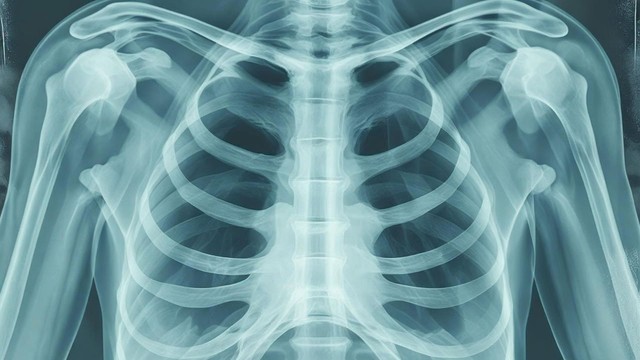

X quang